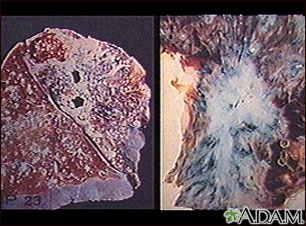

Tuberculosis is caused by a group of organisms: Mycobacterium tuberculosis, M bovis, M africanum and a few other rarer subtypes. Tuberculosis usually appears as a lung (pulmonary) infection. However, it may infect other organs in the body. Recently, antibiotic-resistant strains of tuberculosis have appeared. With increasing numbers of immunocompromised individuals with AIDS, and homeless people without medical care, tuberculosis is seen more frequently today. (Image courtesy of the Centers for Disease Control and Prevention.)